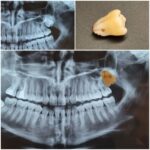

عدم استفاده از دو دندان سالم مجاور به عنوان پایه در ایمپلنت گذاری؛ آنگونه که در روش بریج استفاده میشود و امکان آسیب دیدن و در نهایت از دست رفتن آنها را بیشتر میکند، کاشت ایمپلنت، از آسیب به دندانهای مجاور ممانعت میکند و نیز وجود فیکسچر در استخوان فک، پدیده تحلیل استخوان فک را به میزان چشمگیری کاهش میدهد.

در بعضی موارد مراجعه دیرهنگام فرد برای کاشت دندان (ایمپلنت) یا وجود کیست و تومورهای دهانی منجر به از بین رفتن فضای مناسب و کم شدن قطر و ارتفاع استخوان فک میشود که در این حالت، دندانپزشک قبل یا همزمان با جایگذاری فیکسچر، با استفاده از پودر و بلاک استخوانی و ممبرین (بایومتریالها) استخوان را بازسازی کرده تا شرایط مناسب برای قرارگیری ایمپلنت مهیا گردد. در این مواقع طول درمان بیمار (آماده شدن استخوان برای جایگذاری ایمپلنت) بسته به شرایط بیمار از ۳ تا ۶ ماه طول میکشد و دندانپزشک به کمک عکسهای رادیوگرافی میتواند روند درمان را دنبال کند و بهترین زمان را برای کاشت ایمپلنت تشخیص دهد.